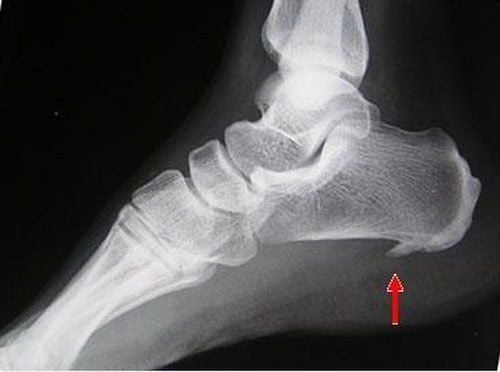

Khi bị gai xương gót chân, ngoài các triệu chứng lâm sàng, việc chẩn đoán cụ thể là chụp phim X quang vùng gót chân để phát hiện hình ảnh gai xương gót chân trên X quang. Cụ thể:

- Chụp X quang vùng gót chân để xem có phải có gai nhọn nhỏ mọc từ mặt dưới xương gót ở vùng gan chân không.

- Phát hiện những tổn thương khác nguy hiểm hơn cũng gây đau xương gót như viêm nhiễm xương, gãy xương hoặc có thể là u xương gót hay áp xe phần mềm tại chỗ.

- Bên cạnh đó, khi xương gót và các gân cơ bám vào xương gót, cân gan chân phải chịu áp lực quá mức sẽ dẫn đến viêm mạn tính quanh gân, viêm cân gan chân. Điều này khiến cho cơ thể phải bù trừ bằng cách lắng đọng canxi để bao bọc vị trí tổn thương, tạo nên gai xương gót chân trên X quang.